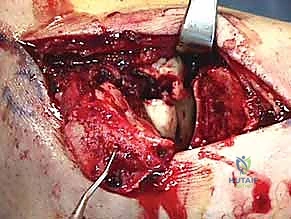

المرحلة الثالثة: التنظيف والرد (Reduction)

بعد كشف العظم المكسور، يقوم الدكتور هطيف بحذر شديد بتنظيف منطقة الكسر من التجلطات الدموية، والأنسجة المتمزقة، وشظايا العظام الصغيرة التي قد تعيق التئام الكسر.

هنا تبدأ المرحلة الأهم: "الرد". باستخدام أدوات دقيقة، يتم إعادة القطع العظمية المكسورة إلى مكانها التشريحي الأصلي بدقة مليمترية. يتم تثبيت القطع مؤقتاً باستخدام أسلاك كيرشنر (K-wires) الدقيقة.